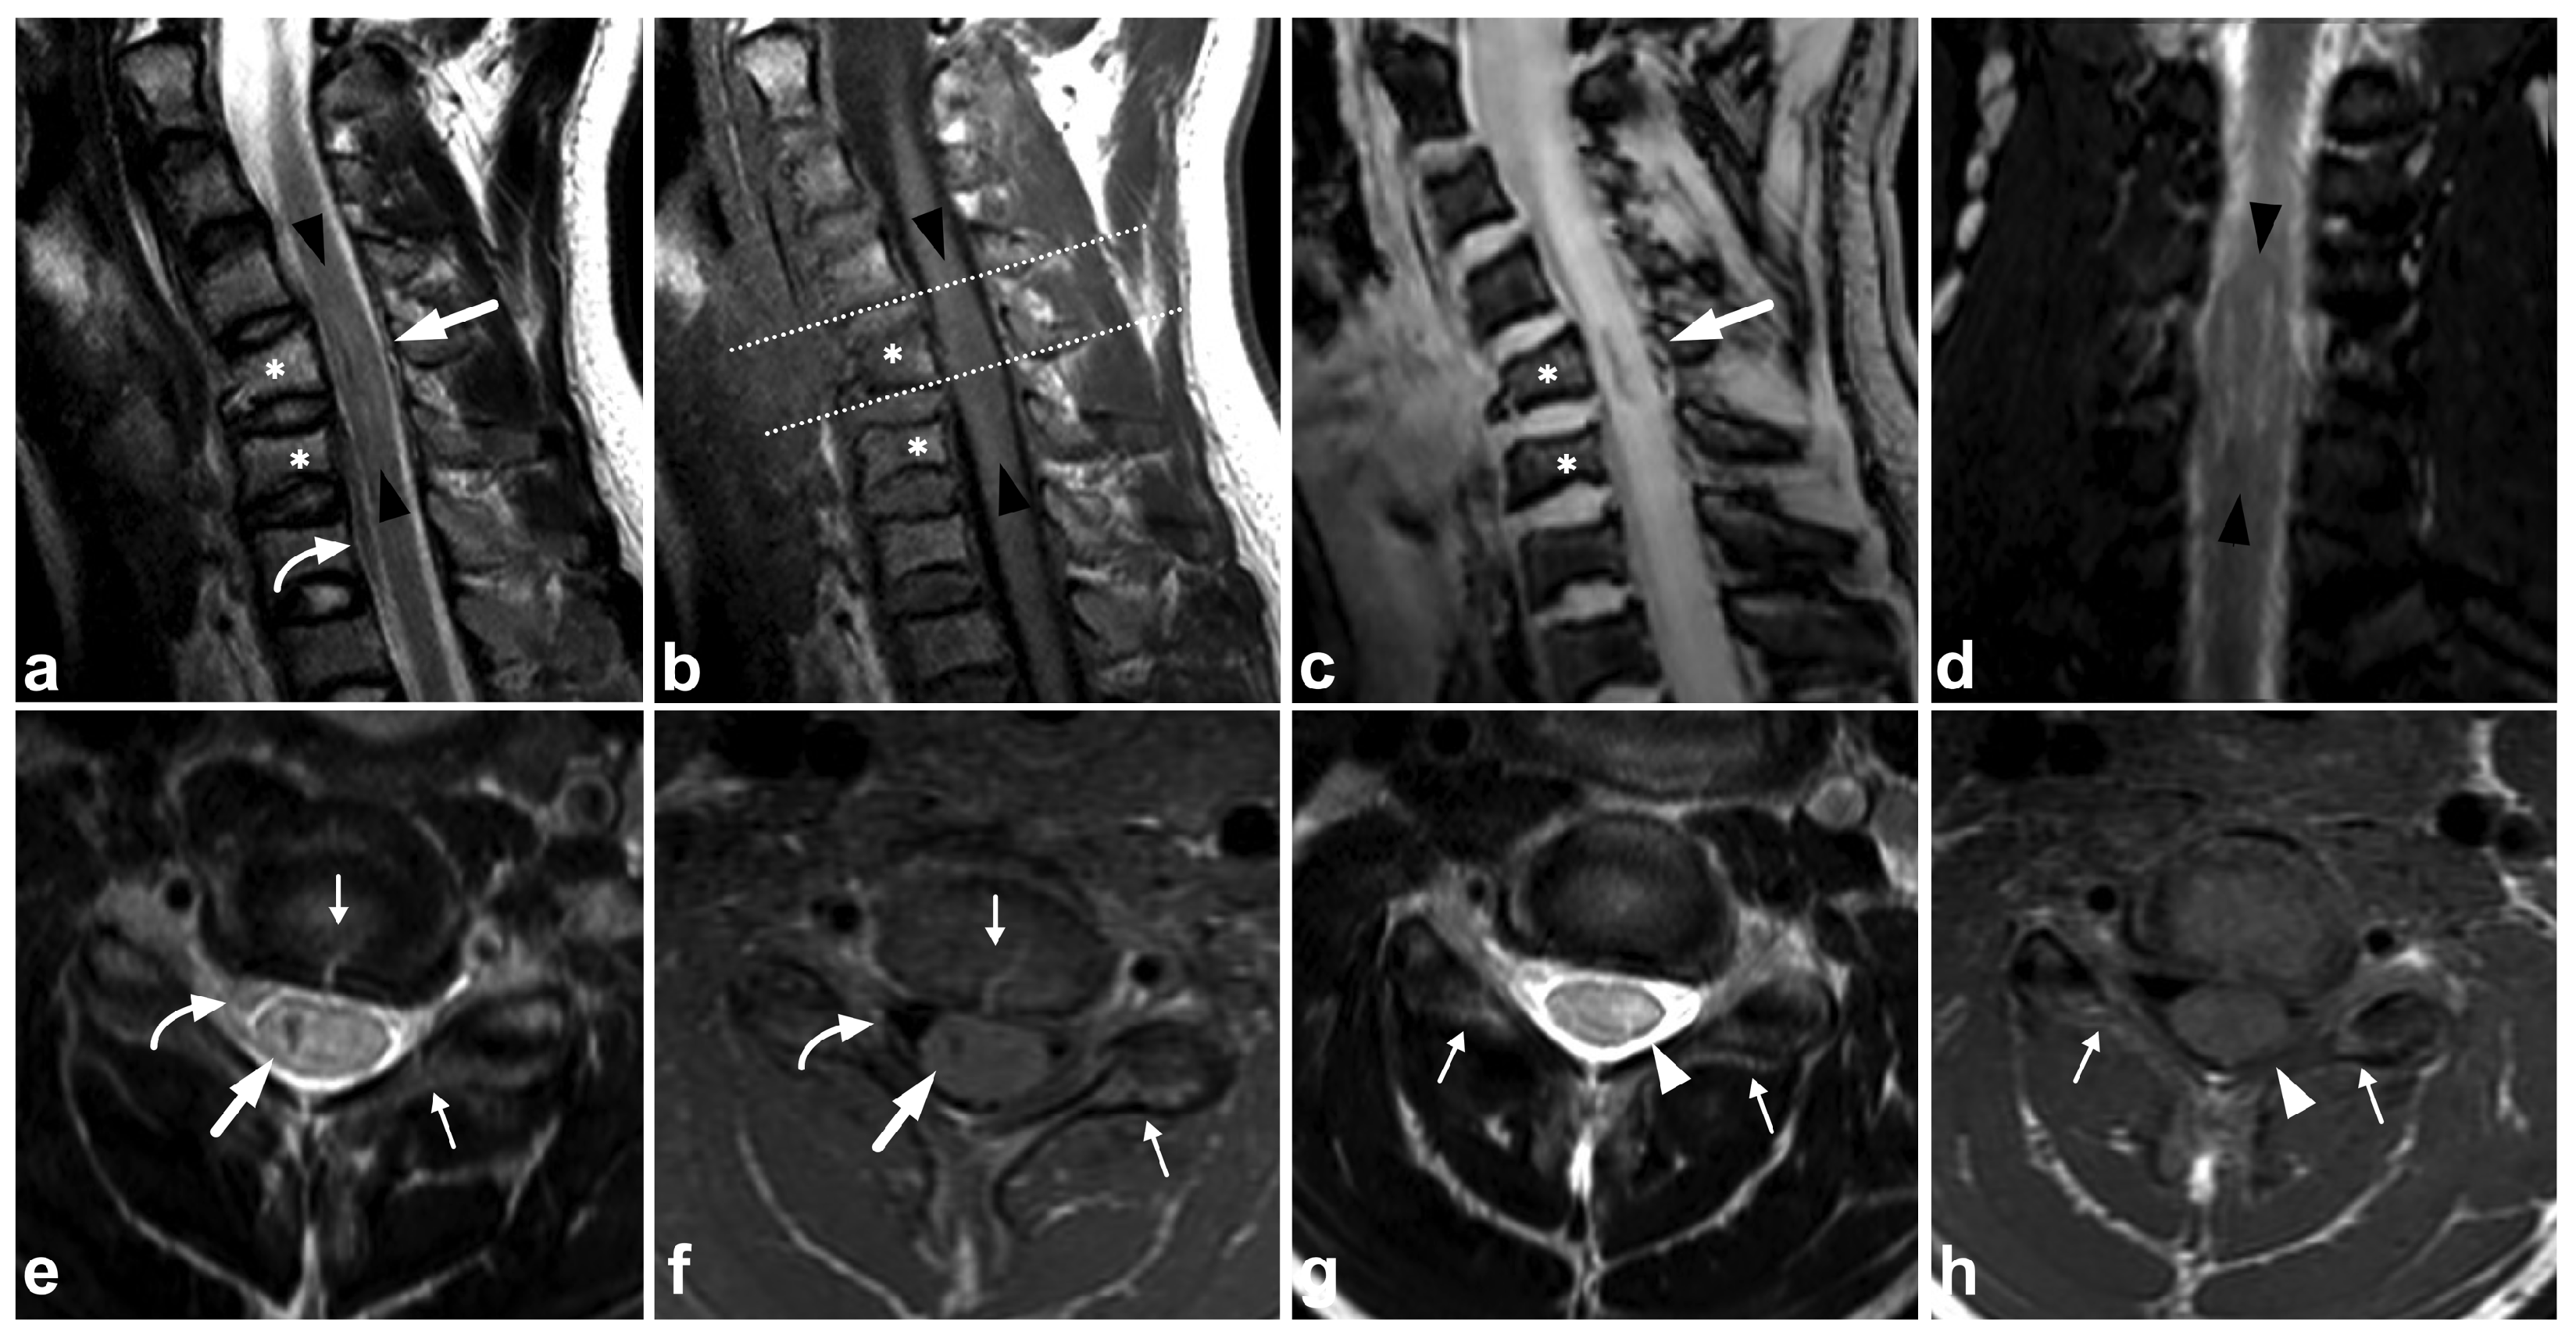

6. Spinal Cord Injuries